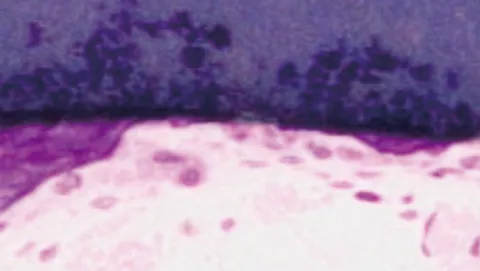

ウサギの上顎部位に4ヶ月埋植したメンブレンの様子。軟組織とメンブレンの境界面において、優れた組織統合を示している。

硬組織側

ウサギの上顎部位に4 ヶ月埋植したメンブレンの様子。骨とメンブレンの境界部において、新生骨(紫)がメンブレン(青)と直接接触していることがわかる。